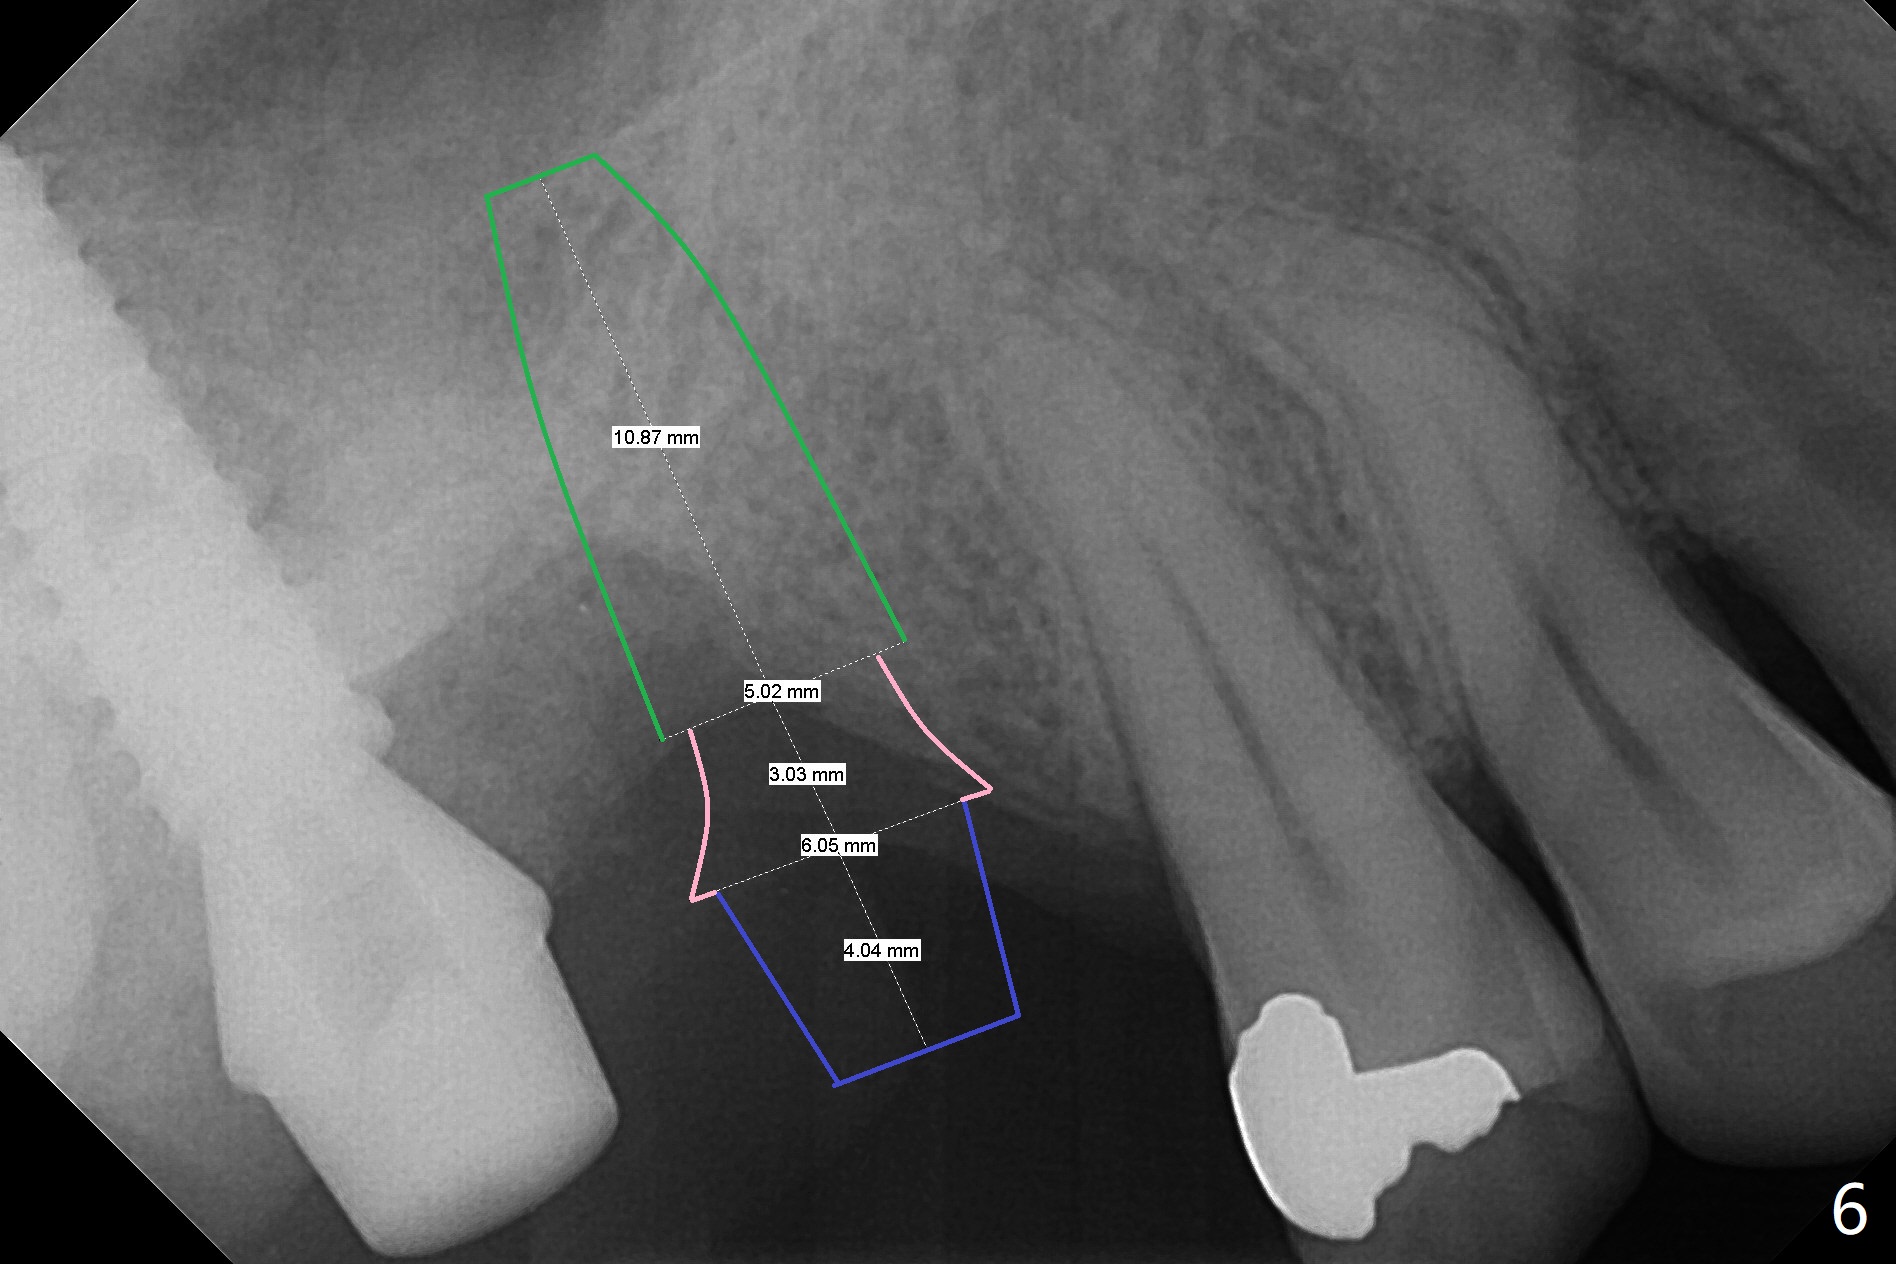

It is difficult to use hard tissue landmark (drill stopper) to make osteotomy in the fresh extraction socket because of socket irregularity and hemorrhage. Once osteotomy is initiated, depth is more reliably controlled with soft tissue landmark (such as gingival margin). This happens in today's case. Without CT information, the osteotomy is established in the buccal slope of the septum of the tooth #2 (after extraction) by using alternatively Magic Sinus Lifter and 4.8 mm Magic Drill (MD). Finally the sinus floor (Fig.1 red dashed line) is lifted after the MD reaches ~16 mm counting from the gingival margin, consistent with preop panoramic X-ray and intraop PA measurement. The 4.5x11 mm dummy implant is close to the impacted 3rd molar (1). Following use of Lindamann bur to move the osteotomy mesially, a 5x9 mm dummy implant is placed away from the 3rd molar (Fig.2 (3: residual root of the 1st molar)). The latter is intentionally not removed in order to maintain osteotomy integrity. A 5x13 mm IBS implant is placed with >50 Ncm; a 6.5x4(4) mm abutment is hand tightened (Fig.3). The remaining large socket is filled with Vera Graft (Fig.4 *). Two months postop, the abutment changes to 6.5x5.7(2) mm without provisional (Fig.5). Nearly 3 months postop, the patient will return for #3 residual root extraction and implant placement with incision (Fig.6). Osteotomy will be initiated in a slope. Prepare surgical round bur for flattening. After placement of a healing abutment, periodontal dressing is to be applied. Take photos to show gingival adaptation to the new abutment without implant exposure at #2.